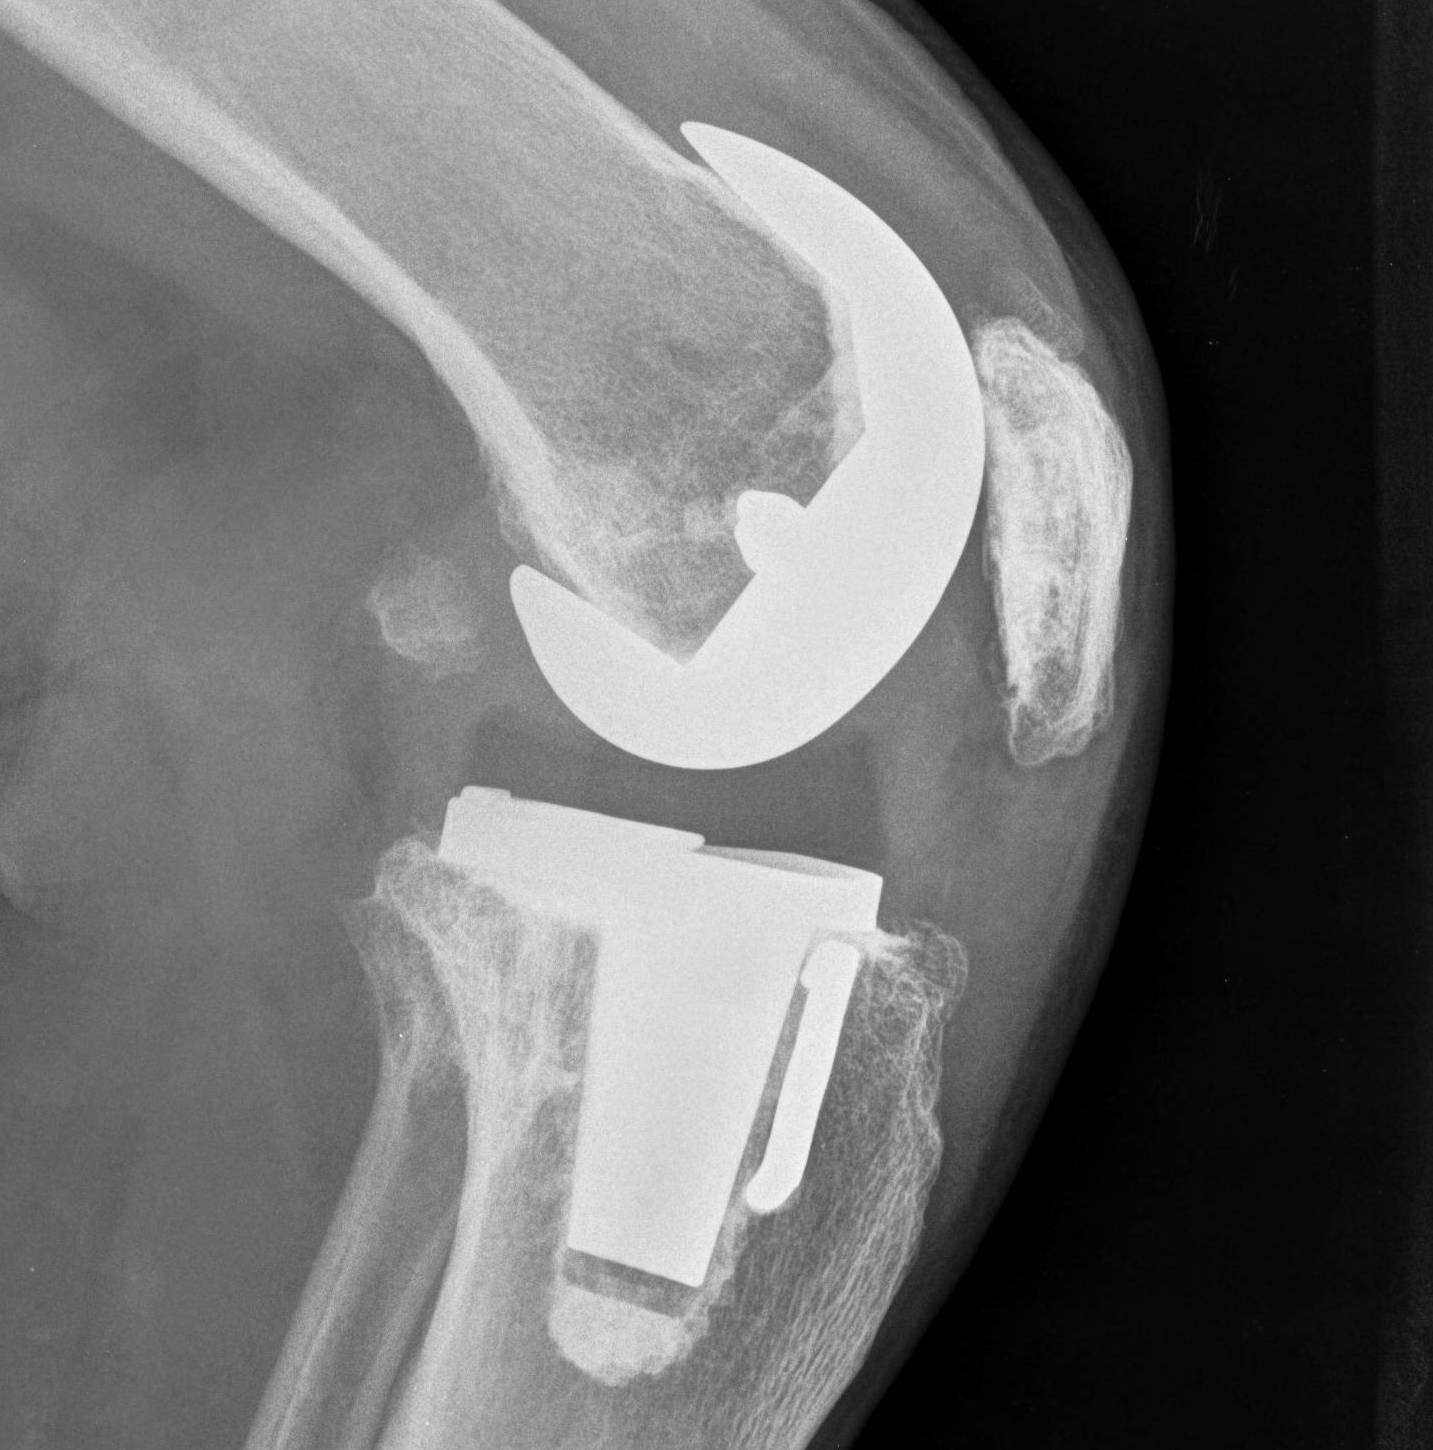

3. Patella Baja

Problem

- patella eversion and exposure difficulties

- PT at risk for avulsion

- may need to consider quadriceps snip / osteotomy